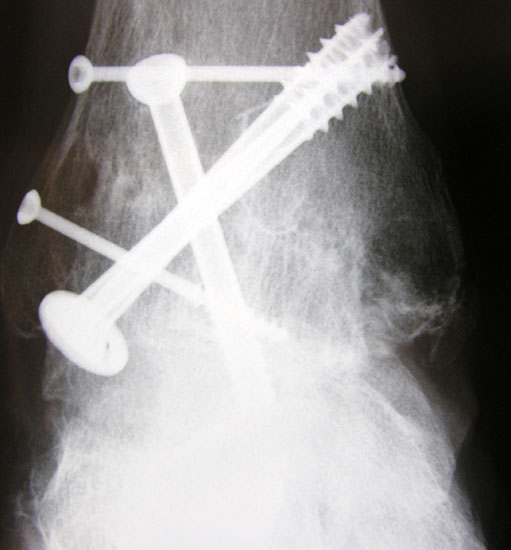

Erreichen eines schmerzfreien oberen Sprunggelenkes mit belastbarem und plantigrad aufsetzbarem Fuss (Abb. 1a und b) unter Verzicht auf die Bewegungsfunktion des oberen Sprunggelenkes. Operative Resektion der arthrotisch veränderten Gelenkflächen bis in den subchondralen frischen Knochen von Tibia und Talus. Fusion mittels Kompressionsschrauben oder Arthrodeseplatten, bedarfsweise Arthrodesenagel.

Abbildung 1b

Fixation mit mindestens 2, ggf. 3 kanülierten Schrauben (6,0, 6,5 oder 7,0 mm), die von medial-kranial und lateral-kranial nach kaudal oder von anterior-kranial nach posterior-distal (Abb. 6) in den Talus unter BV-Kontrolle in 2 Ebenen eingebracht werden (Sabo 2014). Im amerikanischen Sprachraum ist die Verwendung der von dorsal-lateral paraachillär nach anterior-medial in den Corpus tali gerichteten Zugschraube geläufig („home run-screw“) (Abb. 7). Es ist darauf zu achten, das untere Sprunggelenk nicht mit Schrauben zu perforieren. Idealerweise spannen die Kompressionsschrauben, deren Gewindegänge nur im Talus liegen sollten diesen stabil in die Malleolengabel ein.